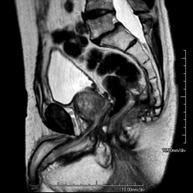

Prova diagnòstica no invasiva que consisteix en l'obtenció d'imatges d'alta definició anatòmica de la pelvis mitjançant l'ús d'un camp electromagnètic i ones de ràdio (amb un emissor i un receptor). No utilitza radiació ionitzant. Es realitza per a l'estudi de patologies d'úter, d'ovari, de trompes i de vagina, ja siguin d'origen tumoral, inflamatori o vascular. També permet valorar les estructures adjacents localitzades a la pelvis i la identificació de les seves alteracions. De vegades és necessari l'ús de contrast intravenós (Gadolini) per caracteritzar les lesions. - RM Pelvis masculina

Prova diagnòstica no invasiva que consisteix en l'obtenció d'imatges d'alta definició anatòmica de la pelvis masculina mitjançant l'ús d'un camp electromagnètic i ones de ràdio (amb un emissor i un receptor). No utilitza radiació ionitzant. No requereix preparació prèvia. En algunes ocasions necessita l'ús de contrast paramagnètic (Gadolini) per caracteritzar les lesions. Aquesta prova permet valorar òrgans com la bufeta urinària, la unió entre els urèters i la bufeta, la pròstata, les vesícules seminals, la uretra i els ossos de la pelvis, entre d'altres. - RM de Fetge

Prova diagnòstica no invasiva que consisteix en l'obtenció d'imatges d'alta definició anatòmica del recte mitjançant l'ús d'un camp electromagnètic i ones de ràdio (amb un emissor i un receptor). No utilitza radiació ionitzant. Normalment no requereix l'ús de contrast paramagnètic (Gadolini). Està indicada principalment en el diagnòstic, l'estadiatge i el seguiment del Càncer de recte. - RM de Paret abdominal